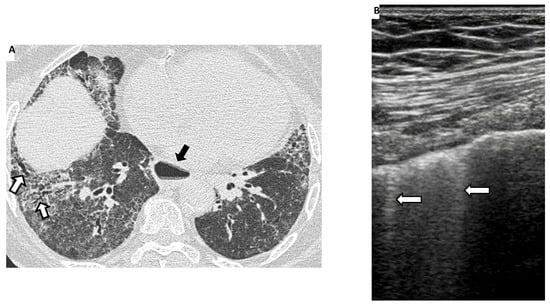

4. Lung Ultrasound

Lung Ultrasound in SSc-ILD: Qualitative Evaluation

- Ferro, F.; Delle Sedie, A. The use of ultrasound for assessing interstitial lung involvement in connective tissue diseases. Clin. Exp. Rheumatol. 2018, 36 (Suppl. 114), 165–170. [Google Scholar]

- Reyes-Long, S.; Gutierrez, M.; Clavijo-Cornejo, D.; Alfaro-Rodríguez, A.; González-Sámano, K.; Cortes-Altamirano, J.L.; Muñoz-Louis, R.; Cruz-Arenas, E.; Camargo, K.; Gonzalez, F.; et al. Subclinical Interstitial Lung Disease in Patients with Systemic Sclerosis. A Pilot Study on the Role of Ultrasound. Reumatol. Clin. 2019, 17, 144–149. [Google Scholar] [CrossRef] [PubMed]

- Delle Sedie, A.; Carli, L.; Cioffi, E.; Bombardieri, S.; Riente, L. The promising role of lung ultrasound in systemic sclerosis. Clin. Rheumatol. 2012, 31, 1537–1541. [Google Scholar] [CrossRef]

- Gutierrez, M.; Salaffi, F.; Carotti, M.; Tardella, M.; Pineda, C.; Bertolazzi, C.; Bichisecchi, E.; Filippucci, E.; Grassi, W. Utility of a simplified ultrasound assessment to assess interstitial pulmonary fibrosis in connective tissue disorders--preliminary results. Arthritis Res. Ther. 2011, 13, R134. [Google Scholar] [CrossRef] [PubMed] [Green Version]

- Pinal-Fernandez, I.; Pallisa-Nuñez, E.; Selva-O’Callaghan, A.; Castella-Fierro, E.; Simeon-Aznar, C.P.; Fonollosa-Pla, V.; Vilardell-Tarres, M. Pleural irregularity, a new ultrasound sign for the study of interstitial lung disease in systemic sclerosis and antisynthetase syndrome. Clin. Exp. Rheumatol. 2015, 33 (Suppl. 91), S136–S141. [Google Scholar]